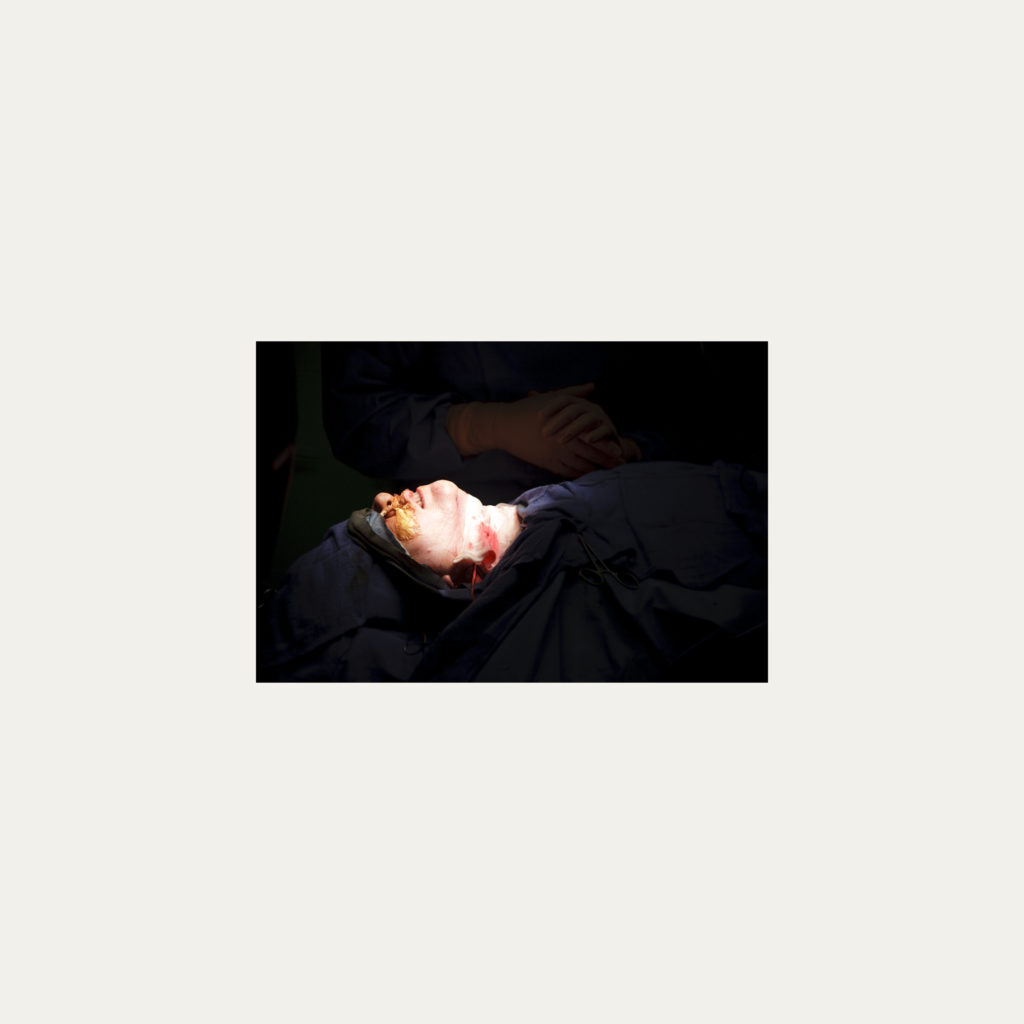

« Nature Morte » est la recherche de l’instant, pendant une intervention chirurgicale où la tête du patient opéré se retrouve seule dans le champ photographié. Aucune main intervenant, peu d’instruments chirurgicaux visibles, laissent le fragment de corps opéré existé pour lui-même. Les têtes, ainsi isolées, en deviennent presque des objets.

Cette approche est intensifiée par la présentation : dans de grands cadres carrés et passe-partout blancs, les photos de petit format font référence aux papillons épinglés de la collection d’un entomologiste.

Face à ces images, une forme de recueillement est nécessaire, s’approcher doucement pour s’approprier tous les détails des images.

Le caractère éminemment esthétique est souligné/donné par les gammes de couleur, la lumière précise sur la tête photographiée, les brillances partielles, renforçant également l’aspect pictural, les textures réelles.

L’humain présent dans ces images est celui qui rompt avec l’invisible et donne à voir l’architecture même de sa chair.